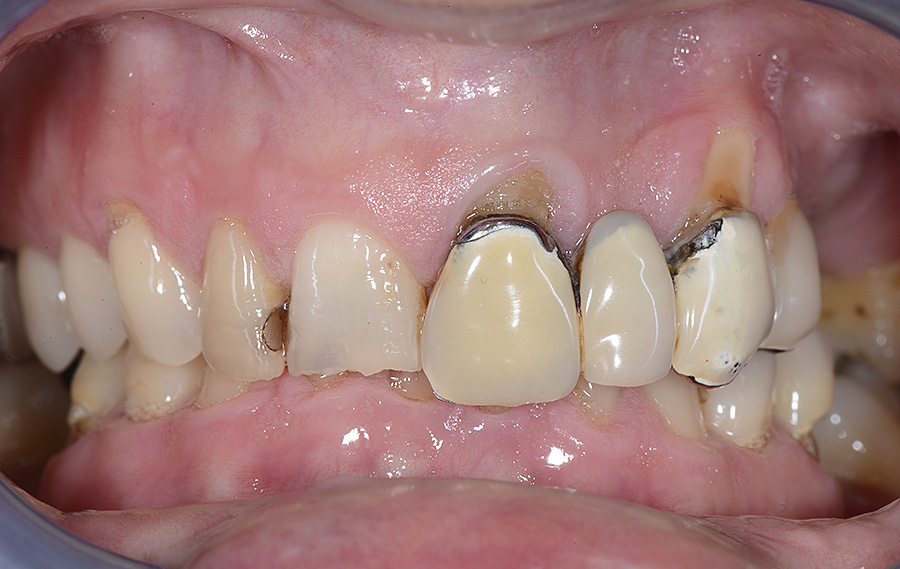

PREMESSA: in seguito all’estrazione dell’incisivo laterale superiore di destra, resasi necessaria per cause batteriche, si decide di affrontare il caso con il posizionamento di un impianto in sostituzione dell’elemento mancante dopo guarigione del sito infetto. Con tecniche rigenerative sia dei tessuti ossei mancanti a causa dell’infezione pregressa, sia dei tessuti gengivali che appaiono inizialmente troppo spostati in alto, si ripristina una corretta morfologia delle parabole (contorni) gengivali e delle papille interdentali (triangoli di gengiva tra due denti vicini).

Vengono utilizzati 2 tipi di provvisori: il primo, cementato ai denti vicini, viene utilizzato dal momento dell’estrazione del dente fino ad impianto osteointegrato (circa 6 mesi); il secondo, avvitato direttamente all’impianto, ha una funzione di prova estetica ma soprattutto di guida per la maturazione dei tessuti gengivali peri-implantari portandoli verso la maturazione completa prima di posizionare la corona finale in disilicato di litio.